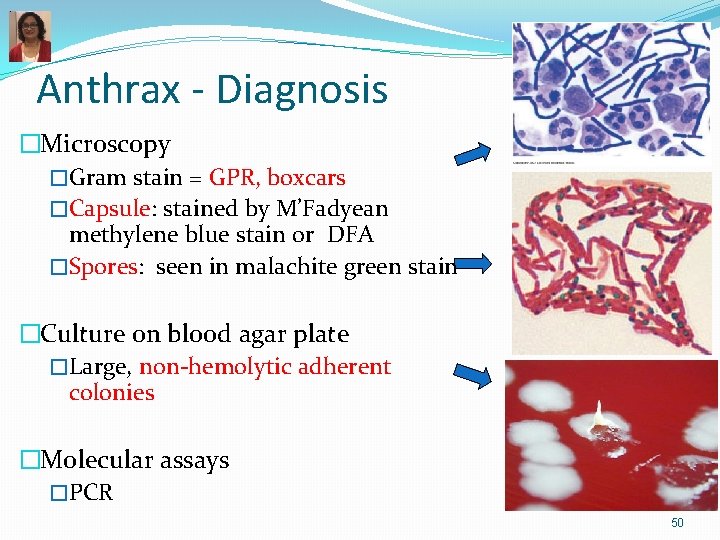

Anthrax - Diagnosis �Microscopy �Gram stain = GPR, boxcars �Capsule: stained by M’Fadyean methylene blue stain or DFA �Spores: seen in malachite green stain �Culture on blood agar plate �Large, non-hemolytic adherent colonies �Molecular assays �PCR 50